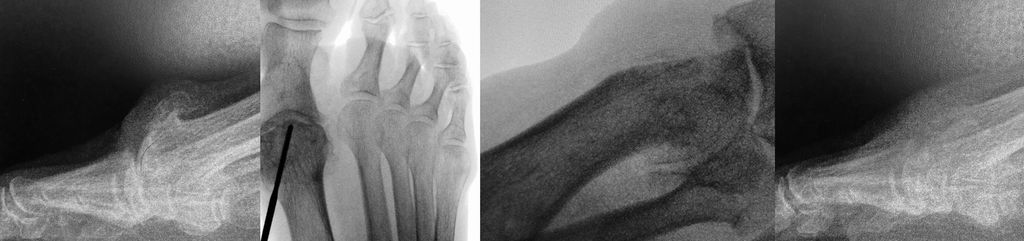

Minimalinvasive distale Metatarsalosteotomie (DMMO)

Aufgrund von Problemen mit der Helal- und der Weil-Osteotomie wurden minimalinvasive Techniken entwickelt. Schon 1991 beschrieb Whitedie minimalinvasive distale Metatarsalosteotomie („Distal Metaphyseal Metatarsal Osteotomy“, DMMO).13 Die Endposition des Metatarsalköpfchens wird durch den Zug der intakten Weichteile und die postoperative Vollbelastung diktiert. Vor allem de Prado, Redfern und Vernois haben diese Technik propagiert. Hier wird unter Zuhilfenahme einer minimalinvasiven Fräse mit hohem Drehmoment eine extraartikuläre Osteotomie des Metatarsales von proximal plantar nach distal dorsal durchgeführt. Das plantare Fragment wird unter Druck von distal nach proximal verschoben. Postoperative Zügelverbände gemeinsam mit dem intakten Weichteilmantel sollen die Osteotomie in der gewünschten Stellung stabilisieren (Abb. 4).

Johansen et al.14 präsentierten eine randomisierte Studie mit jeweils 30 Patienten. Die Komplikationsrate war bis auf das vermehrte Auftreten von hypertrophen Narben (0 vs. 9%) in der offenen Weil-Gruppe gleich. Die postoperative Bewegungseinschränkung, die „floating toe“ und eine Plantarflexions- bzw. Hyperextensionsfehlstellung traten bei der offenen Weil-Osteotomie häufiger auf. Die Operationszeit war bei der DMMO-Gruppe signifikant kürzer, dafür war die Röntgenbestrahlungszeit signifikant länger.

Krenn15 und Palmanovich8 zeigten in der Analyse ihrer ersten Patienten die Lernkurve dieser Technik auf und wiesen auf die Notwendigkeit von speziellen Operationskursen hin.